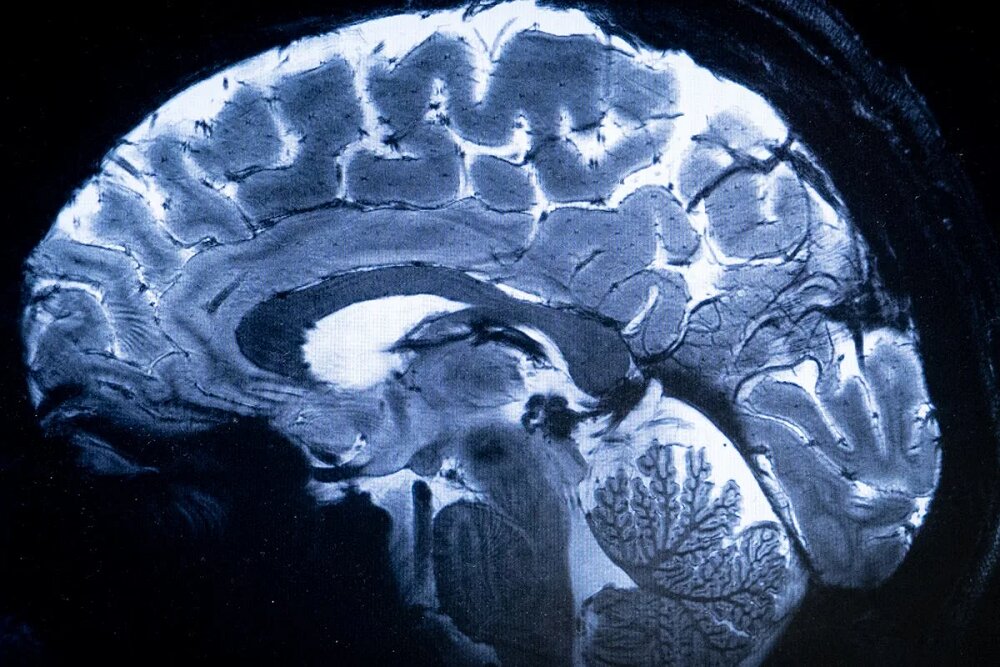

چهاردهمین کنگره علوم اعصاب پایه و بالینی با حمایت ستاد توسعه علوم و فناوری‌های شناختی از ۱۹ آذر در تهران گشایش می یابد.

به گزارش مگ دید، چهاردهمین کنگره علوم اعصاب پایه و بالینی به منظور توسعه فعالیت‌های پژوهشی، تبادل آخرین دستاوردها و یافته‌ های تحقیقاتی و نیز گسترش تعامل و همکاری میان محققان، متخصصان و پژوهشگران با حمایت ستاد توسعه علوم و فناوری‌های شناختی از ۱۹ تا ۲۱ آذرماه در محل مرکز همایش‌های بین المللی رازی دانشگاه علوم پزشکی ایران برگزار می شود.

این کنگره با محوریت “پزشکی شخصی سازی شده”، فرصت مناسبی را برای محققان، پزشکان، دانشجویان و متخصصان فعال در زمینه علوم اعصاب پایه و بالینی فراهم می سازد تا در محیطی پویا به بحث و تبادل نظر، انتقال تجربه و اندیشه ورزی بپردازند و از این رهگذر پیوند بین تحقیقات علوم پایه و کاربردهای بالینی را در فضایی بین رشته ای تقویت کنند.

ارائه جدیدترین دستاوردهای علمی و نتایج تحقیقاتی با حضور متخصصان برجسته داخلی و بین‌المللی در تمامی رشته‌های مرتبط از مهندسی تا پزشکی و علوم انسانی از رویکردهای این گردهمایی تخصصی به شمار می رود.